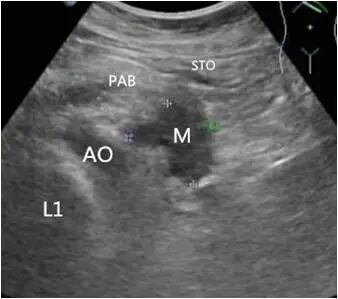

胰体尾部癌

第二种表现为胰腺内肿物不规则或有分叶状的团块回声,肿块边界不清,轮廓不整,向周围组织呈蟹足样或锯齿样浸润。

第三种表现为较小的肿块,内部大多数为均匀低回声,后方声衰减不明显;较大肿瘤呈混合回声,后方回声衰减,也可以看到坏死液化的无回声区。